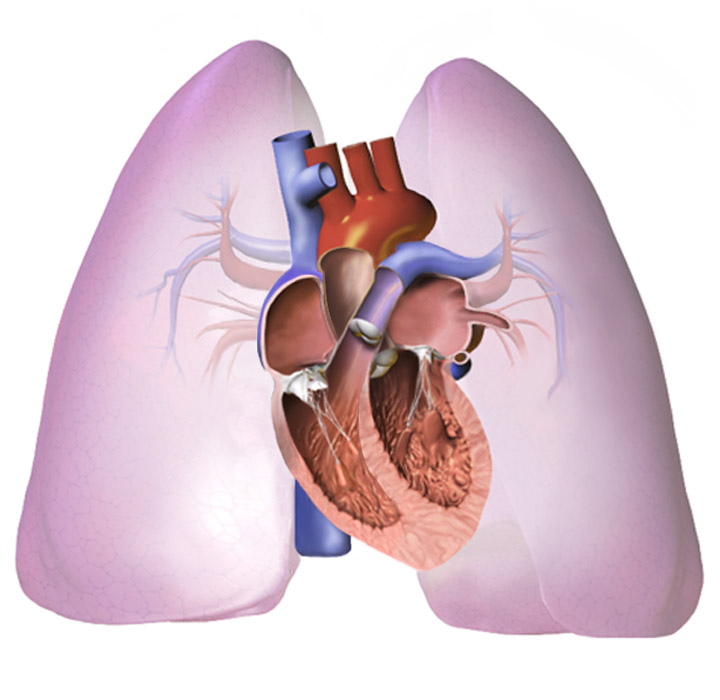

폐암은 폐에 비정상적인 암세포가 증식하여 덩어리를 형성하고 인체에 해를 미치는 것을 말합니다. 즉 폐에 생긴 악성종양을 말하며 폐 자체에 암이 발생하거나 다른 장기에서 생긴 암이 폐로 전이되어 발생합니다.

폐암으로 인해 폐를 둘러싼 흉막에 흉수가 차고, 종양이 기관지를 막거나 흉수에 의해 폐포의 공기가 급속히 빠지는 등의 이유로 호흡곤란이 유발됩니다. 흉부 통증 폐암은 흉부 통증을 유발합니다.

폐암이 흉막과 흉벽을 침범하여 통증이 생기고 암이 더욱 진행되면서 통증이 지속됩니다.